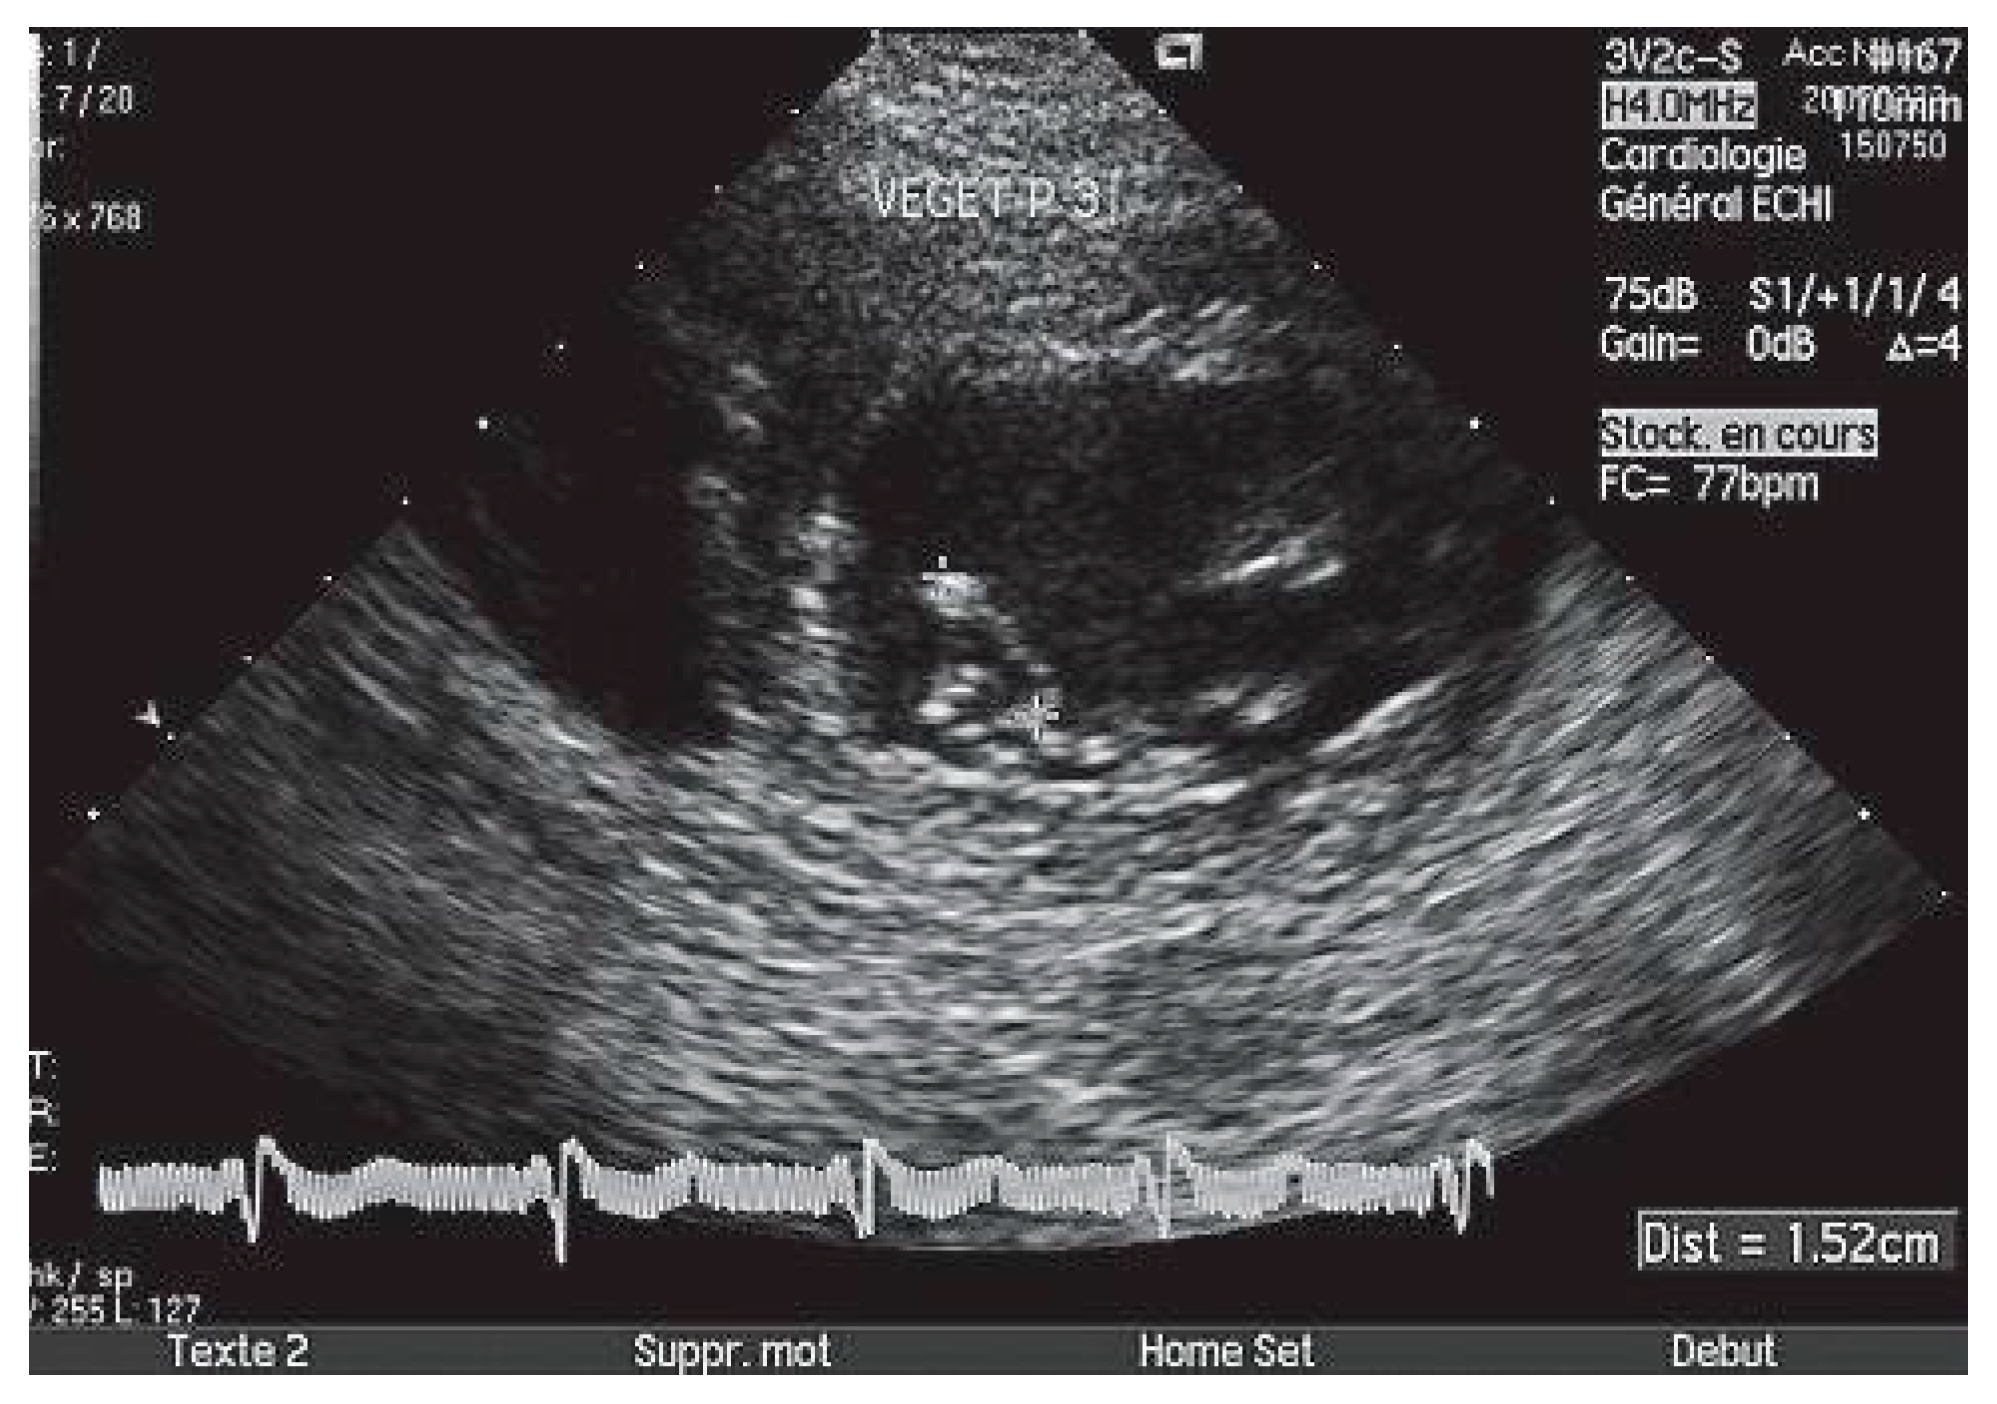

Végétations infectieuses

L’endocardite infectieuse explique 3% des accidents emboliques, dont 2⁄3 sont des embolies cérébrales [32]. La performance diagnostique de l’ETO est excellente, très supérieure à celle de l’ETT (Figure 3), en particulier pour les végétations de petite taille (<5 mm) [33] et sur les prothèses valvulaires mécaniques.

La prévalence des AVC varie dans l’endocardite infectieuse de 15 à 20% [32], les végétations de plus de 10 mm, mobiles, étant associées à un fort risque embolique [34].

Figure 3. Végétation en bâton de tambour, de plus de 5 mm, sur le segment P3 de la valve mitrale postérieure, visualisée en ETT (fenêtre parasternale petit axe).